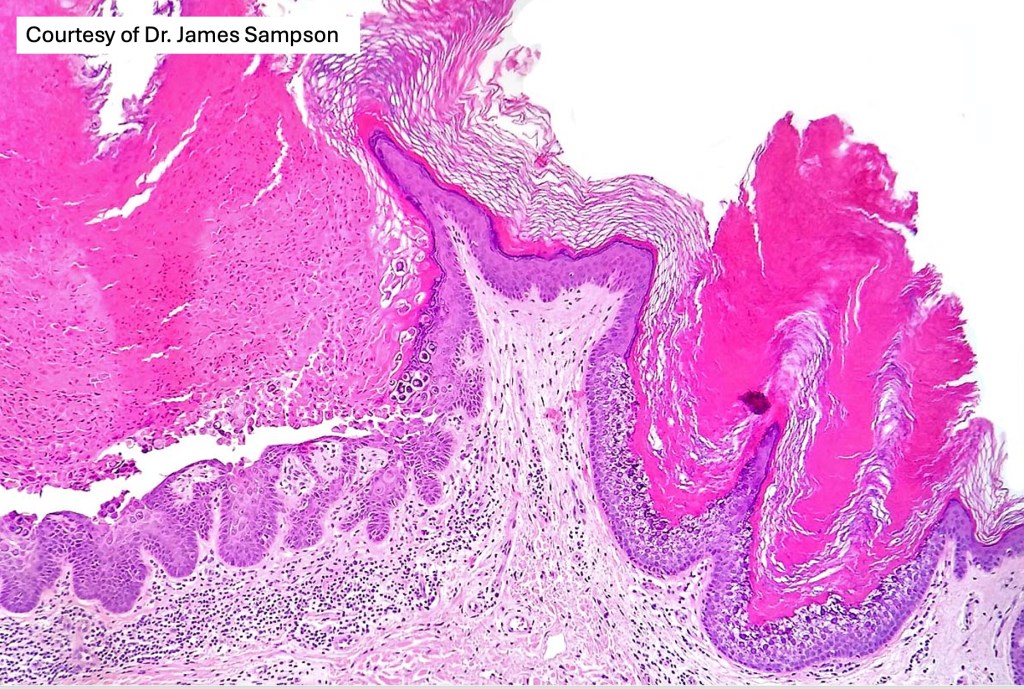

•Cup-shaped circumscribed lesion showing hyperkeratosis, focal parakeratosis & acanthosis

•Superficial epidermis shows often multifocal keratinocyte vacuolation with eosinophilic cytoplasmic inclusions & sometimes epidermal necrosis